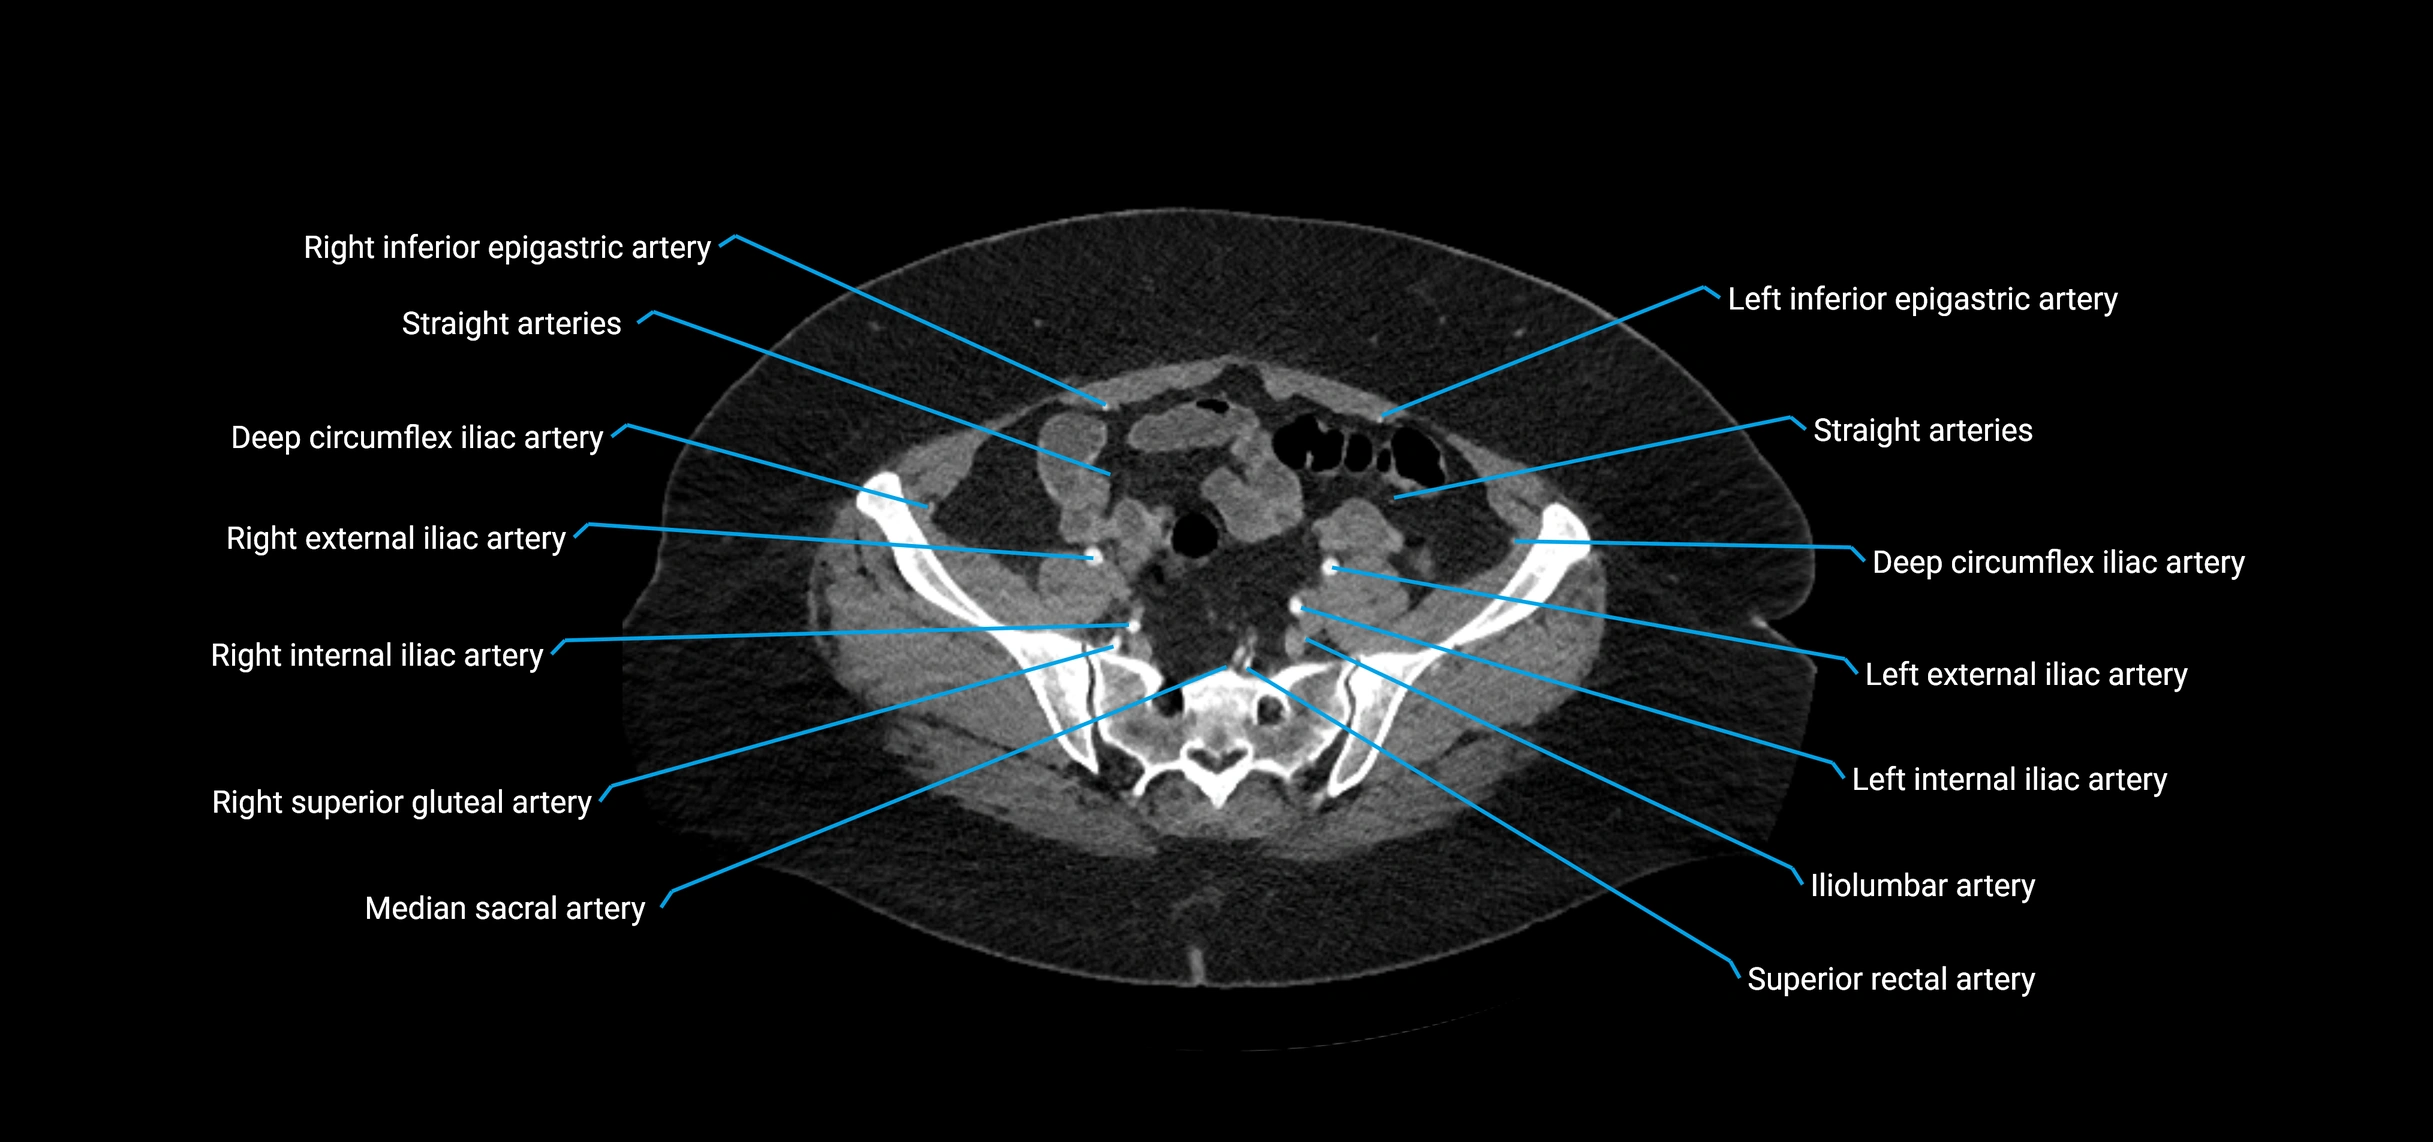

CT images

image

Contrast-enhanced CT (CTA):

• Gold standard for abdominal aortic imaging

• Provides excellent detail of lumen, wall, aneurysm, thrombus, and branch vessels

• Multiplanar and 3D reconstructions help in aneurysm measurement, stent graft planning, and dissection evaluation